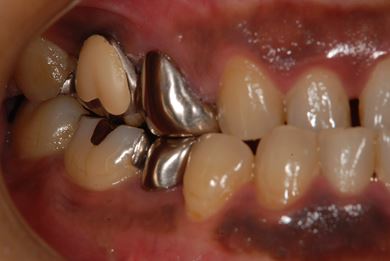

治療前

• 治療前